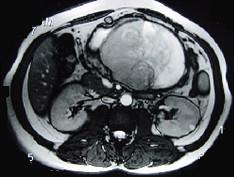

问题 男,36岁,腹胀、消化不良、消瘦、中上腹痛,影像检查如下图,最可能的诊断是 ( )

选项 A.胃间质肉瘤并肝转移 B.胃间质瘤并原发性肝癌 C.内胚窦瘤肝转移 D.胃淋巴瘤伴原发性肝癌 E.胃间质瘤并肝血管瘤

答案 A